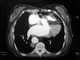

Azygos continuation of inferior vena cava

The azygos vein is a vein running up the right side of the thoracic vertebral column draining itself towards the superior vena cava. It connects the systems of superior vena cava and inferior vena cava and can provide an alternative path for blood to the right atrium when either of the venae cavae is blocked. [Source: Wikipedia ]